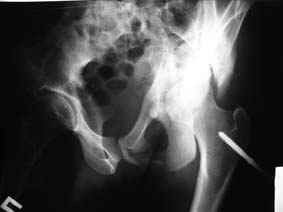

Это обзорные и косые снимки